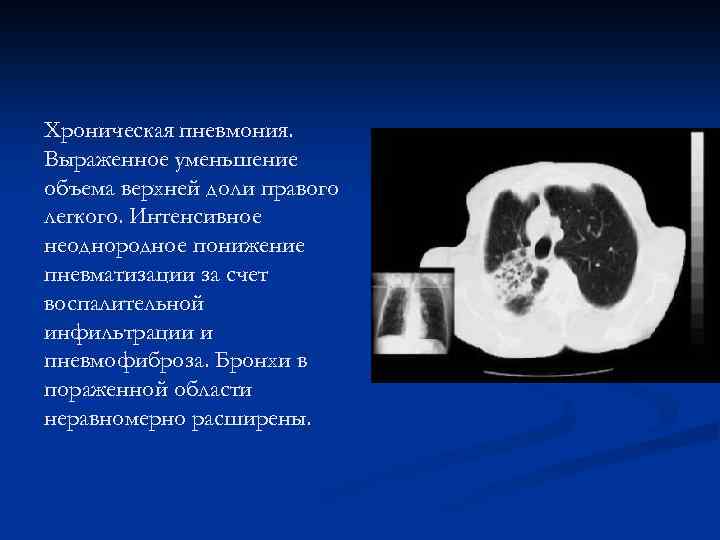

Хроническая пневмония. Выраженное уменьшение объема верхней доли правого легкого. Интенсивное неоднородное понижение пневматизации за счет воспалительной инфильтрации и пневмофиброза. Бронхи в пораженной области неравномерно расширены.